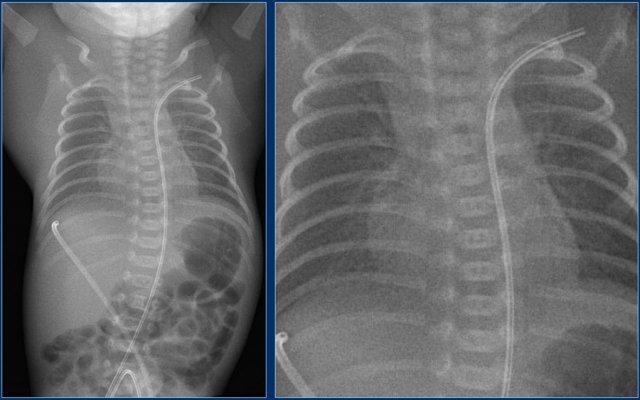

Các phát hiện bao gồm:

- Đường truyền tĩnh mạch rốn quá sâu.

Đường truyền có thể đã đi qua lỗ bầu dục thông, qua nhĩ trái và vào tĩnh mạch phổi.

- Sau khi điều chỉnh lại, đầu catheter ở vị trí phù hợp.

Lưu ý rằng ống nội khí quản vẫn còn đặt quá sâu.